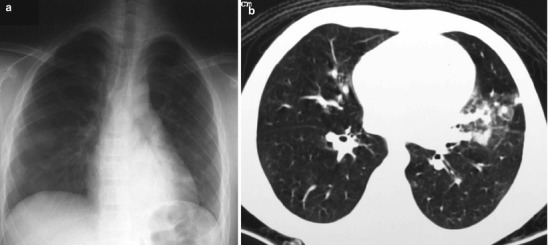

Certain groups of viruses have been recently reported to cause severe respiratory infection leading to respiratory failure and even death. The severe acute respiratory syndrome (SARS) caused by coronavirus A (SARS-CoV) created a scare in 2003 with over 8,000 cases reported from 29 different countries. SARS presents with a prodrome of flu-like illness, followed by cough, dyspnea, and possibly acute respiratory distress. The initial radiographic manifestation is the presence of focal or diffuse interstitial opacities but rapidly progresses to bilateral areas of consolidation (Thibodeau and Viera 2004) (Fig. 13.3). Another pandemic virus is the influenza virus A H5N1 (avian influenza virus), originating from Asia and spreading over many parts of the world from 2003 to 2007. More recently, influenza virus of swine origin, designated as influenza A H1N1, was first reported in Mexico in 2009 and has rapidly spread globally. Symptoms range from asymptomatic infection to mild upper respiratory illness, viral syndrome, diarrhea, severe pneumonia, acute respiratory distress syndrome (ARDS), and progression to multiorgan failure. Initial chest radiographs in children with a mild and self-limited clinical course are often normal, but they may demonstrate prominent peribronchial markings with hyperinflation and multifocal areas of consolidation (Lee et al. 2010) (Fig. 13.4).

Fig. 13.3.

SARS infection. Chest radiograph of a 13-year-old boy 3 days after the onset of fever shows ill-defined haziness in bilateral lower zones (a). An 8-year-old boy with confirmed SARS shows an area of mixed ground-glass opacity with consolidation in the lingula on HRCT (b) (Cases courtesy of Winnie CW Chu, MD, from Hong Kong)

Fig. 13.4.

AH1N1 virus pneumonia. Frontal chest radiograph shows generalized increase interstitial markings with multifocal patchy infiltrates (Case courtesy of Xanthe Marie Javier MD, from Philippines)